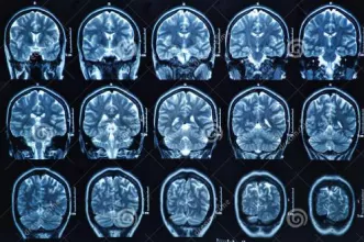

MRI也就是磁共振成像,屬于斷層成像的一種,它是利用磁共振現(xiàn)象從人體中獲得電磁信號,并重建出人體信息。通過檢查可獲得橫斷面、矢狀面、冠狀面的影像,空間分辨率高,是神經(jīng)系統(tǒng)、脊柱脊椎部分檢測的第一選擇。

無論是DR還是CT,由于對部分軟組織的分辨率不足,所以軟組織疾病的排查便成了它們的短板,而磁共振的長處恰恰就是清晰顯示軟組織疾病,對于膀胱、直腸、子宮及關(guān)節(jié)肌肉的檢查優(yōu)于CT。MRI適用于神經(jīng)系統(tǒng)病變、心血管系統(tǒng)、胸部病變、全身軟組織病變等。